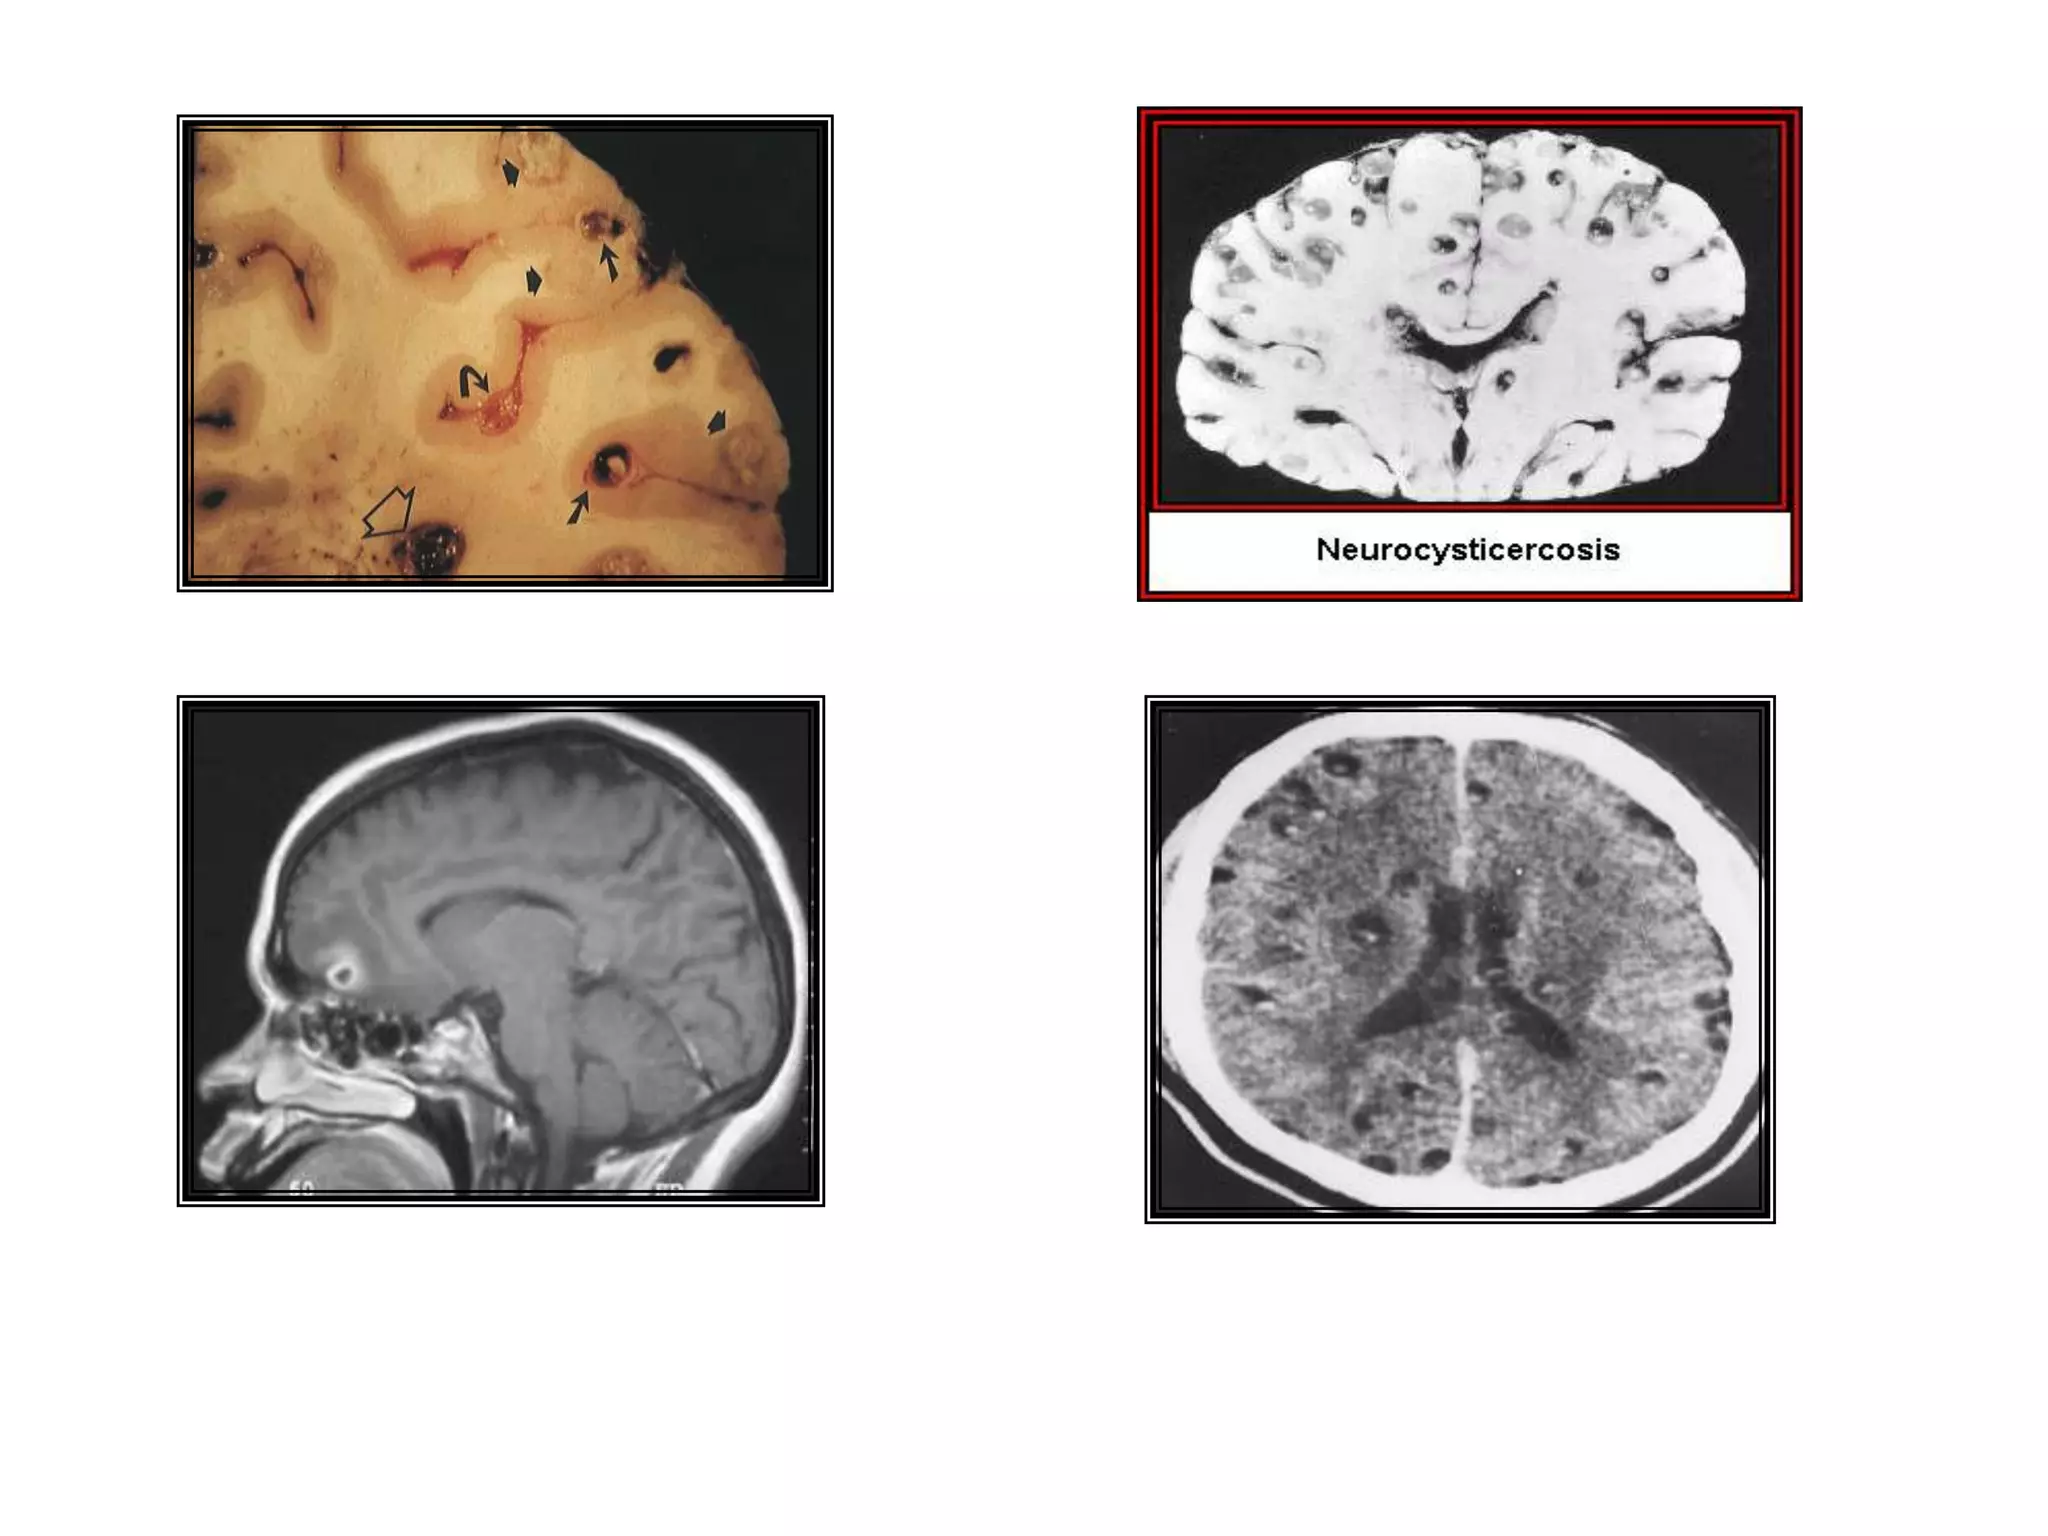

TAENIA SOLIUM2 – 7 mts x 1.5 cmsArmada (22-32 ganchos, en 2 coronas)Proglotides mas largos que anchosÚtero en forma de saculaciones con 7 a 12 ramas a cada ladoHuevos típicos

HUESPEDES DEFINITIVOS:HombreLOCALIZACION:Intestino delgadoHUESPED INTERMEDIARIO:Cerdos domésticos y salvajes, Ocasional/ hombre.NOMBRE DE LA LARVA:Cisticercus cellulosaeLOCALIZACION DE LA LARVA:	Tejido muscular, nervioso y diversos órganos

Hacinamiento.DESARROLLO DE CISTICERCOSLos cerdos jóvenes son más susceptibles a la infección que los adultos (Metacéstodos mas viables en encéfalo)Cisticercus alcanza en 20 días el tamaño de la cabeza de un alfiler. (esbozo de escólex)

Músculos de color pálido, gris-rojizo, blandos, húmedos y con variado número de cisticercos.

Vesículas compactas del tamaño y aspecto de grano de arroz, con liquido acuoso en su interior y en el centro un punto blanco opaco.

¿ Radiaciones Gamma sobre el metacéstodo?DIAGNÓSTICO Dx Clínico difícil.

Antemorten: examen visual y palpación lengua.

Dx Preciso: Necropsia.